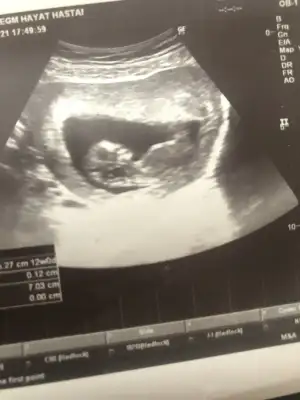

Merhaba lutfen yardimci olurmusunuz 11 hafta 6 gunluk karindan ultrason

• IMG-20210206-WA0007.webp

IMG-20210206-WA0007.webp

19,1 KB · Görüntüleme: 69